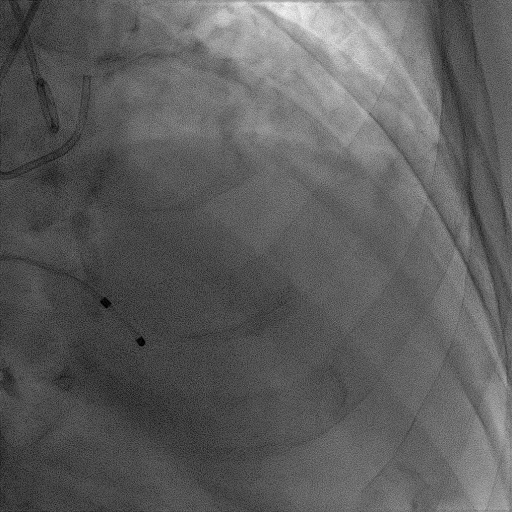

手术过程

患者麻醉方式为全麻,建立静脉通路后,穿刺右侧股静脉,预埋ProGlide缝合器,食道超声指导下房间隔穿刺成功,将Superstiff导丝送至左房,应用18F鞘管扩张穿刺部位,沿导丝将导引导管送入左房,MitraClip调整后顺利到达二尖瓣目标位置,在X线及食道超声辅助下,将Mitraclip NTR成形夹精确定位后,成功夹合二尖瓣A2-P2区,超声显示反流明显减少,多切面证实夹合组织充分,肺静脉多普勒波形由反向恢复正常,手术顺利结束,安返普通病房。

术中超声

确定房间隔穿刺点:靠后

2D视图下测量大鞘长度2cm

3D视图打开夹子

X-plane:下第夹子尝试捕获2区

X-plane:测量前叶长25mm,后叶长14.2mm

X-plane:计算前叶捕获长度8mm,后叶捕获长度7mm

3D视图下观察二尖瓣双孔形态

3D-color:残余少量返流